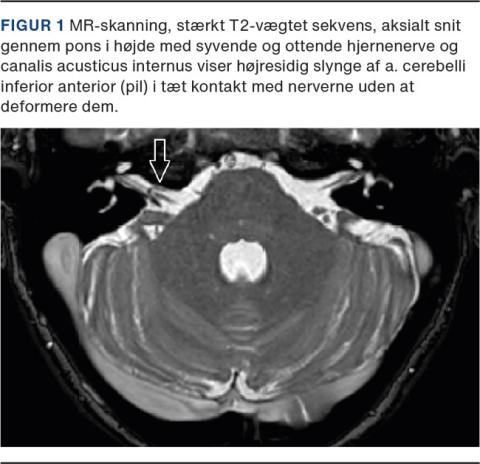

MR-skanning af hjernen samt specialoptagelse af syvende og ottende hjernenerve og porus acusticus internus viste på højre side en tæt kontakt mellem en slynge af a. cerebelli inferior anterior (AICA-slynge) og syvende og ottende hjernenerve (se Figur 1).